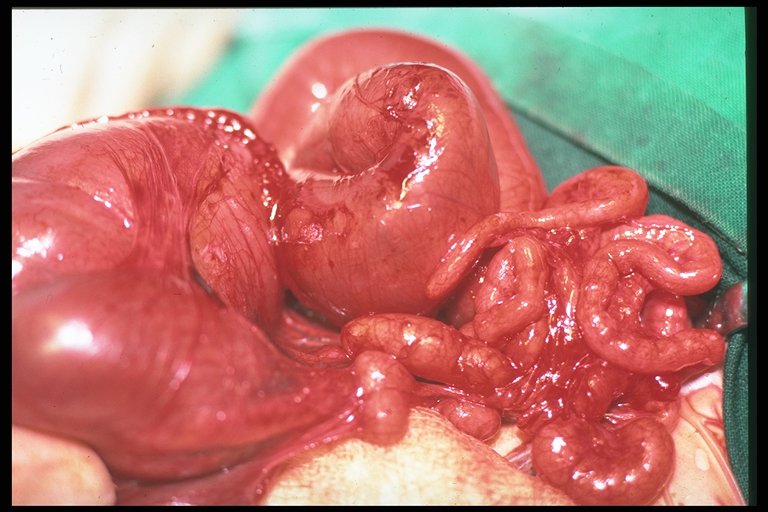

Operative finding of intestinal atresia type IV, marked mesenteric defect is noted. The distal part of intestine with mesenteric defect curls around the feeding vessels - christmas tree or apple peel appearance.